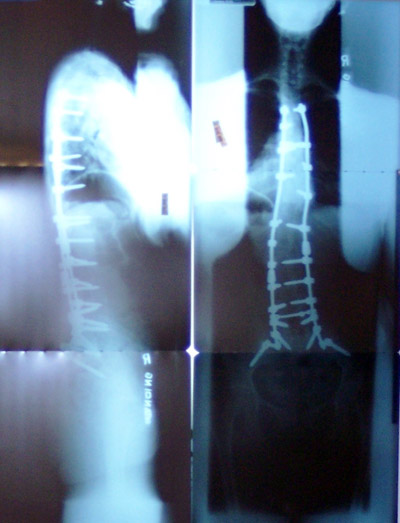

As shown in the next photos, our Ruby, needed surgeries.